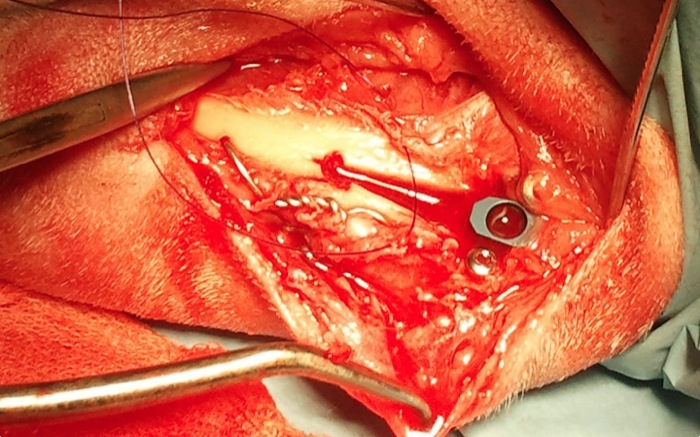

Tras una capsulorrafia lateral estándar eliminamos el ligamento cruzado roto y lavamos con suero. En este caso se realiza también una liberación de menisco medial mediante una miniartrotomía medial. La artrotomía se cerrará y continúa la cirugía a nivel de la cresta tibial desperiostizando minimamente la linea de corte.

Se coloca un cerclaje en ocho que es tensado a cada lado para asegurar la cresta ante la fuerza hacia proximal del sistema del cuádriceps. Son frecuentes las fracturas distales de la cresta al abrir el espacio para la celdilla pero no es un problema dado que el periostio sigue intacto y tenemos el cerclaje de seguridad.